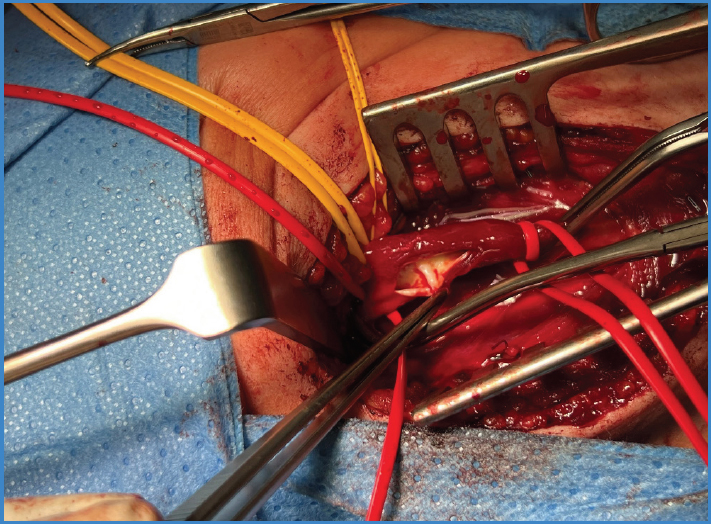

A 37-year-old woman with no significant medical-surgical history presented to the emergency department with a 3-hour history left hemiplegia. A brain CT scan revealed the presence of a right middle cerebral artery infarction, leading to emergency mechanical thrombectomy. During the procedure, an arteriography revealed the presence of a non-occlusive septum in the bulb segment of the right carotid artery, suggestive of a carotid web (Fig. 1). Cardiac origin was ruled out as she had sinus rhythm and an echocardiogram without abnormalities. A CT angiography was requested, confirming the diagnosis. A decision was made to perform right internal carotid endarterectomy (Fig. 2) with closure using an autologous saphenous vein patch. She was discharged after 72 hours uneventfully. At the 6-month follow-up, patency was observed, and there was no re-stenosis.

Carotid web is an intimal protrusion of uncertain prevalence, predominantly seen in women, which is commonly located on the proximal posterolateral face of the internal carotid artery. It is associated with transient ischemic attacks and embolic strokes in young patients without classical cardiovascular risk factors (1). This occurs due to hemodynamic impairment of flow distal to the septum (2). Diagnosis is established through CT angiography or magnetic resonance imaging (3). Surgical treatment, through stenting or endarterectomy, has been shown to reduce the risk of recurrent ischemic episodes, which occur in 26.8 % of symptomatic patients treated exclusively with pharmacological antiplatelet, anticoagulant therapy, or a combination of both (4). Despite the lack of studies on the subject, the relevance of this disease has been increasing, influencing its recent inclusion in the latest European clinical practice guidelines, which recommend surgical treatment with stenting or endarterectomy for symptomatic patients with no other cause to explain their neurological symptoms after a thorough evaluation (level of evidence IIB, grade of recommendation C) (5). In our case, the use of an autologous vein patch for the carotid closure was chosen due to the patient’s age and the lower rate of long-term infectious complications (6).